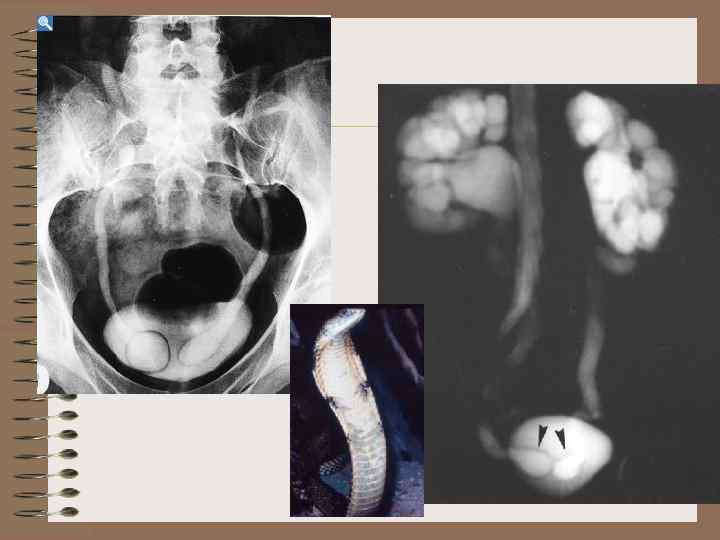

Добавочная третья почка • Крайне редкая аномалия • Две почки расположены в типичном месте • Третья почка имеет самостоятельное кровоснабжение

Аномалии величины Гипоплазия почки • Нормально сформированный орган маленьких размеров • Дифференциальный диагноз со сморщенной почкой • Причина – аномалия сосудов, аномалия закладки метанефроса

Гипоплазия почки • • Размеры уменьшены Структура сохранена Контуры гладкие Дифференциация между паренхимой и срединным эхокомплексом и кортико- медуллярная дифференциация сохранены